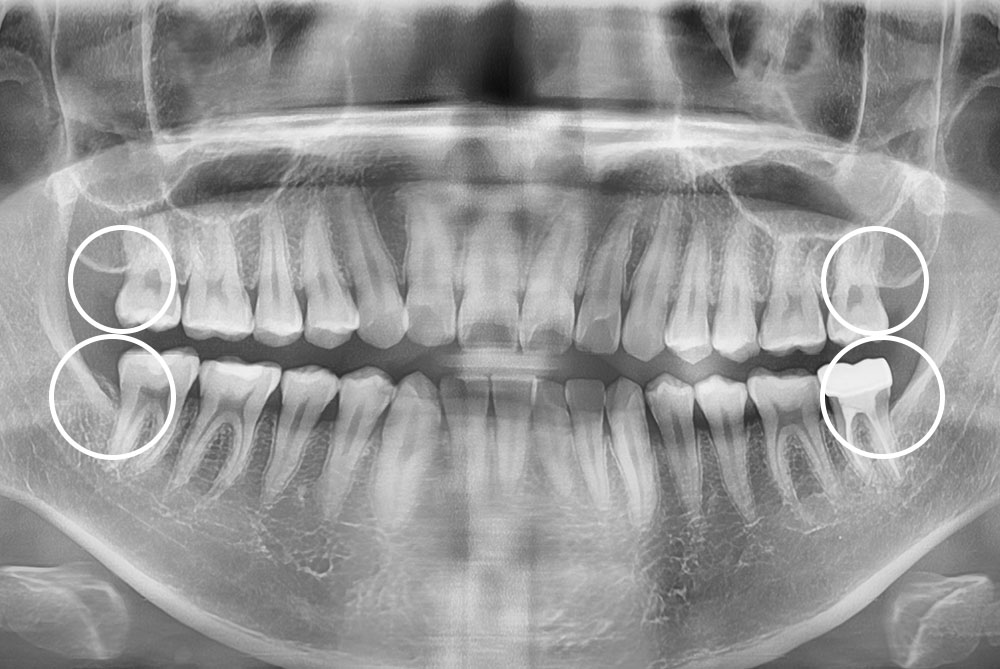

[사랑니] 매복 사랑니 발치

치료전 : 2019-02-26